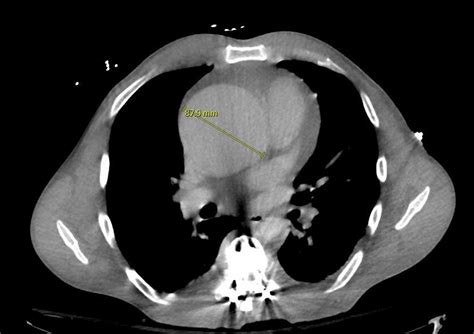

• Computed Tomography (CT) Scan: A CT scan provides detailed images of the aorta and can help identify the extent of dilation and any associated abnormalities.